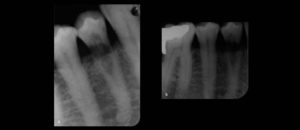

192 – Clasificación propuesta para los contactos interproximales de los molares primarios utilizando CBCT: Un estudio piloto

El «Área de contacto» es un término que se usa para denotar las alturas proximales del contorno de las superficies mesial y distal del diente.